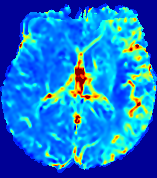

LesionRefer to captionRefer to captionRefer to captionRefer to captionRefer to captionRefer to caption𝐕rgbsubscript𝐕𝑟𝑔𝑏{\bf{V}}_{rgb}Refer to captionRefer to captionRefer to captionRefer to captionRefer to captionRefer to caption𝐕2subscriptnorm𝐕2{\|\bf{V}}\|_{2}Refer to captionRefer to captionRefer to captionRefer to captionRefer to captionRefer to captionRefer to caption3.53.53.52.82.82.82.12.12.11.41.41.40.70.70.70.00.00.0(mm/s)𝑚𝑚𝑠(mm/s)D𝐷DRefer to captionRefer to captionRefer to captionRefer to captionRefer to captionRefer to captionRefer to caption0.0200.0200.0200.0160.0160.0160.0120.0120.0120.0080.0080.0080.0040.0040.0040.0000.0000.000(mm2/s)𝑚superscript𝑚2𝑠(mm^{2}/s)Slice #1Slice #2Slice #3Slice #4Slice #5Slice #6

Figure 4: PIANO feature maps for another patient in the ISLES 2017 training set, where the lesion is located in the right hemisphere. Top row: segmented stroke lesion region (white) on different slices. The corresponding slices for the PIANO feature maps are shown in the following rows.

For a better insight into an estimated velocity field 𝐕𝐕{\bf{V}} and diffusion field 𝐃𝐃{\bf{D}}, we compute the following maps: (1) 𝐕rgbsubscript𝐕𝑟𝑔𝑏{\bf{V}}_{rgb}: Color-coded orientation map of 𝐕=(Vx,Vy,Vz)T𝐕superscriptsuperscript𝑉𝑥superscript𝑉𝑦superscript𝑉𝑧𝑇{\bf{V}}=(V^{x},V^{y},V^{z})^{T}, obtained by normalizing 𝐕𝐕{\bf{V}} to unit length and mapping its 3 components to red, green, blue respectively; (2) 𝐕2subscriptnorm𝐕2\|{\bf{V}}\|_{2}: 222 norm of 𝐕𝐕{\bf{V}}; (3) D𝐷D: scalar field in Eq. 5.

Fig. 3 and Fig. 4 show the PIANO feature maps estimated from two ISLES 2017 patients: all are highly consistent with the lesion in both cases. Details of the blood flow trajectories are revealed in 𝐕rgbsubscript𝐕𝑟𝑔𝑏{\bf{V}}_{rgb} by the ridged patterns and the sharp changes of colors in the unaffected (right) hemisphere, while the flat patterns appearing within the lesion provide little directional information about the velocity and indicate low velocity magnitudes. Velocity magnitudes are more directly visualized via 𝐕2subscriptnorm𝐕2\|{\bf{V}}\|_{2}, from which one can easily locate the lesion where 𝐕2subscriptnorm𝐕2\|{\bf{V}}\|_{2} is low. D𝐷D also indicates lower diffusion values in the lesion, though with less contrast potentially due to the fact that it captures the accumulated effect of CA diffusion at the voxel-level.